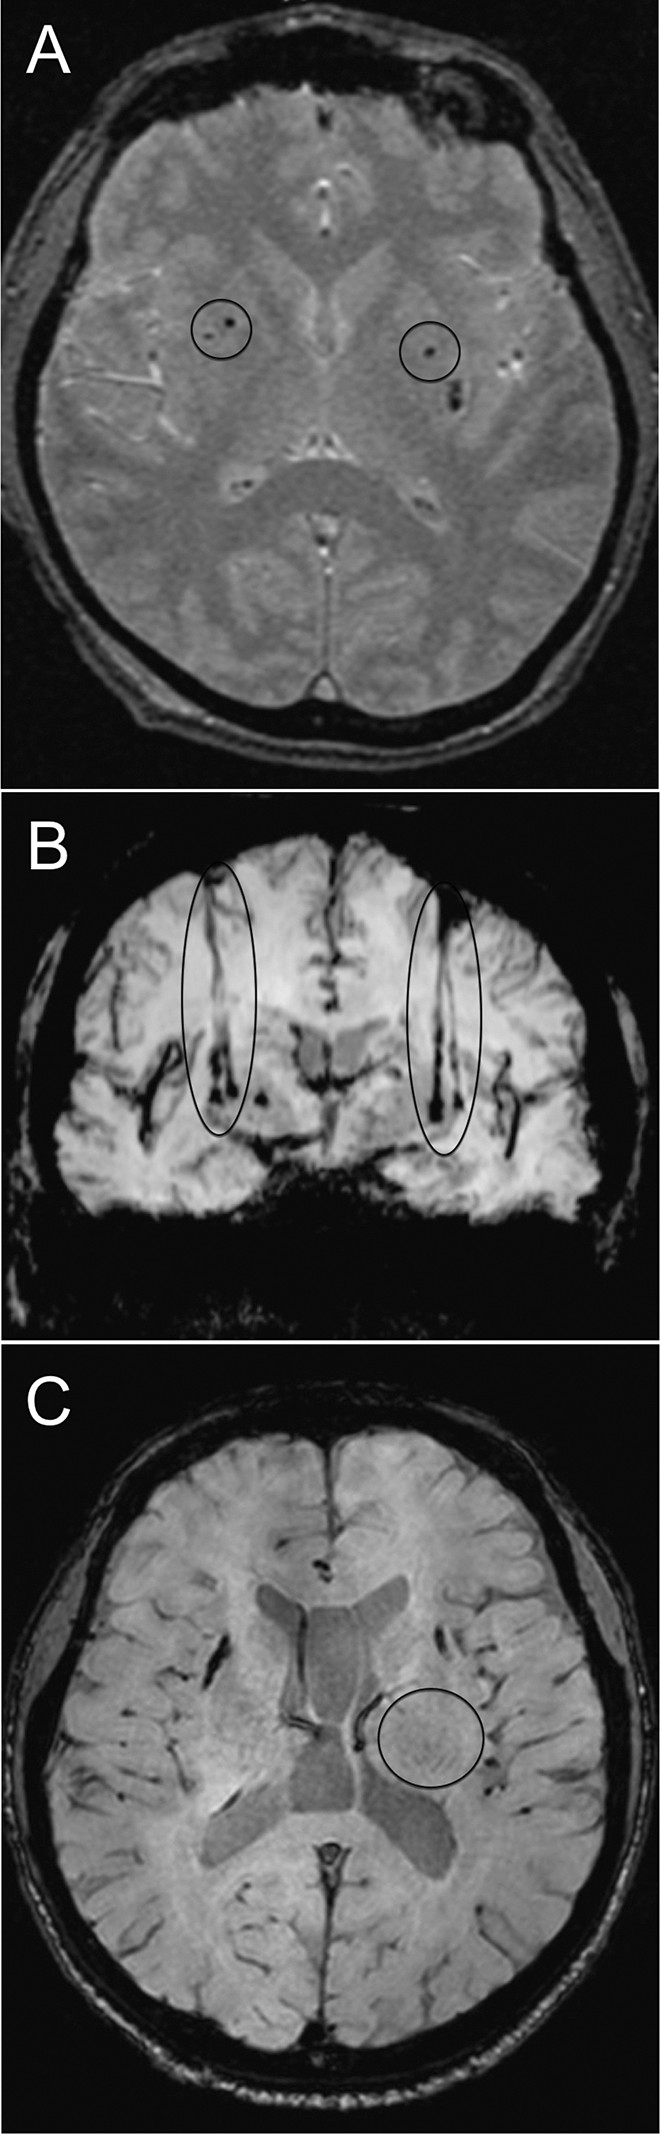

移植患者的代表性腦部 MR 圖像

如圖2所示。細胞植入的位點和軌跡路徑如圖 1 和 2 所示。分別參見圖 2A 和 2B。在1、2和4年隨訪的幾個針跡結束時,在 T2 加權圖像上識別出小簇低信號。在 P4 的年度 MRI 監測中,在右側殼核(圖2C)中觀察到強大的移植物生長,沒有大腦結構的異常。未顯示腫瘤形成的證據。

圖2:移植患者的大腦MR圖像。